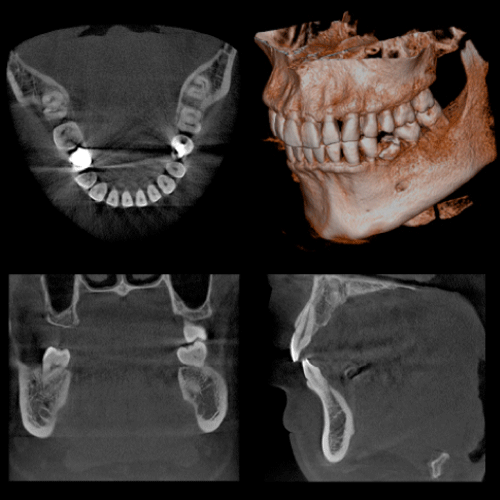

矯正治療とCT

矯正治療では、術前検査で顎骨の状態が正確にわかるので、歯の移動の限界が予測でき、治療計画の立案に非常に有効です。また、近年多く見られる埋伏歯の位置関係についても正確に診断でき、早期牽引治療が可能となります。最適な診査診断および治療方法を確立することは、治療期間の短縮にもつながります。